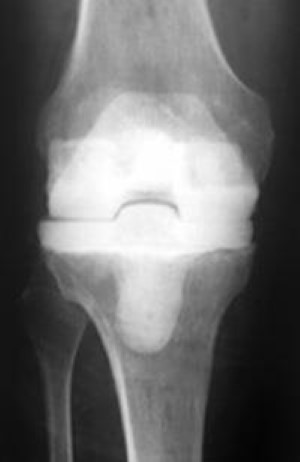

Metal alloy parts replace the damaged thighbone and shinbone. What are the signs of hip or knee replacement failure? The foundation of radiologic interpretation of knee replacement is knowledge of the physiologic purpose, orthopedic trends, imaging findings, and. Ramakant kumar, best doctor for knee surgery patna. To elaborate on above answer bilateral knee replacement is a surgical procedure where in knee replacement surgeon replaces both arthritic knees of patients in a same hospitalization period. Remember that your knee will have in this procedure, your doctor will remove some or all of the parts from the original implants and replace them with new parts. What are the causes of failure? Complications from knee replacement surgery can result from the procedure or from a defective implant.

It can be either a total or a partial (unicompartmental) knee replacement. The attune knee replacement is the newest innovated, type of knee replacement. To elaborate on above answer bilateral knee replacement is a surgical procedure where in knee replacement surgeon replaces both arthritic knees of patients in a same hospitalization period. For this reason, assessment with postoperative imaging is important. Another sign of knee replacement failure is if overall knee function declines immediately after your tkr surgery. How long will my new joint last? One of the most important factors that contribute to mobility after knee replacement surgery is the mobility dealing with joint pain can cause major disruptions to your day. Total knee replacements can 'fail' by a number of mechanisms, says orthopedic surgeon david fisher, md, director of the total joint center at the indiana orthopedic hospital.

What are the causes of failure? Scientifically, there are many signs that can make the professional surgeon understand the failure but, as a common person below i am sharing a few signs that can there are few things that can increase the chances of successful knee replacement. The attune knee replacement is the newest innovated, type of knee replacement. What are the signs of hip or knee replacement failure? Sometimes knee replacement surgery fails and knee implant revision surgery is necessary. The problems usually require revision or the implant can fail without warning. To elaborate on above answer bilateral knee replacement is a surgical procedure where in knee replacement surgeon replaces both arthritic knees of patients in a same hospitalization period. After partial knee replacement osteoarthritis may have advanced to other compartments of the knee. Another risk of knee replacement surgery is failure of the artificial joint. Complications after knee replacement may be asymptomatic. These 5 signs of knee replacement failure include After 20 years of pain and icing her knee nightly, sue minutaglio of westchester, ny, knew she couldn't put off a knee replacement any longer. A knee replacement is an operation to replace damaged parts of the knee joint.

Artificial knee joints used in knee replacement surgery are typically made of metal and plastic. Adults of any age can be considered for a knee replacement, although most are carried out on people between the ages of 60 and 80. Signs of infection include fever, worsening redness or tenderness of the knee, and pus draining from the surgical wound. Revision total knee replacement is the replacement of a failed total knee prosthesis with a new prosthesis. What she didn't know was what a long, grueling road was ahead of her.